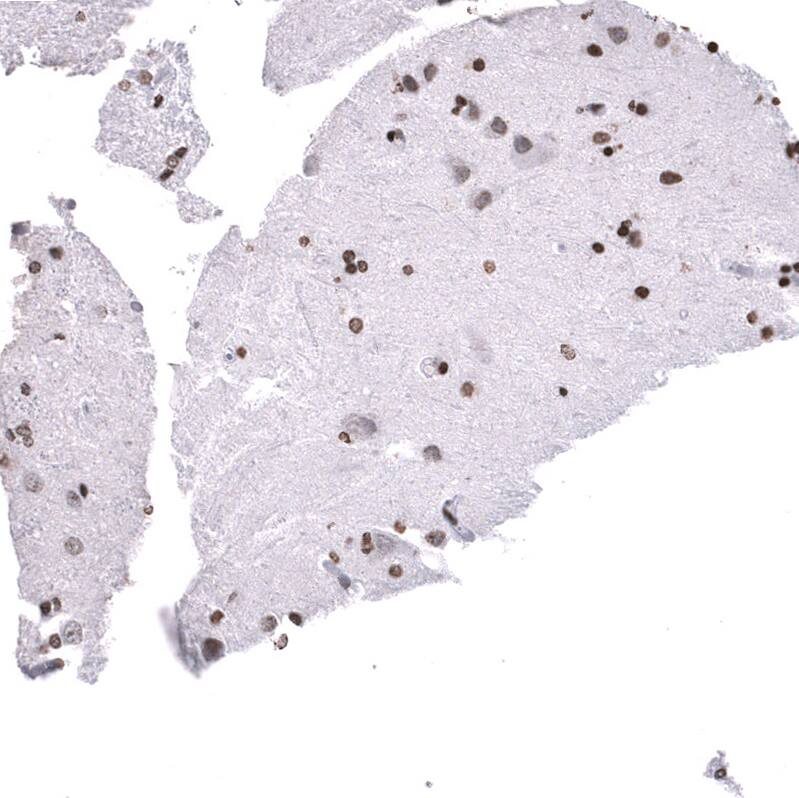

Immunohistochemistry-Paraffin: LHX9 Antibody [NBP3-44343]

Staining of human astrocytoma shows strong nuclear positivity in tumor cells.